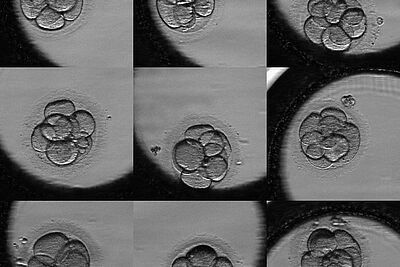

Le Service de Biologie de la Reproduction - CECOS (Centre d'Etude et de Conservation des Ovocytes et du Sperme Humain) prend en charge les infertilités du couple, en collaboration avec l'unité clinique d'Assistance Médicale à la Procréation (AMP ou PMA). Il assure la partie biologique de l'AMP : préparation du sperme pour les inséminations intra-utérines, réalisation de Fécondation in vitro pour permettre la rencontre du spermatozoïde et de l'ovocyte prélevés chez le couple, avec ou sans injection intracytoplasmique (ICSI) ainsi que la congélation d'embryons.

Par ailleurs, pour les patients atteints de cancer, le service assure la cryoconservation des gamètes (spermatozoïdes, ovocytes) ou de tissu germinal avant la mise en route des traitements, afin de préserver leur fertilité future. Le centre d'AMP du CHU présente un niveau élevé d'activité (700 inséminations intra-utérines, 500 fécondations in-vitro, 800 transferts d'embryons après décongélation).